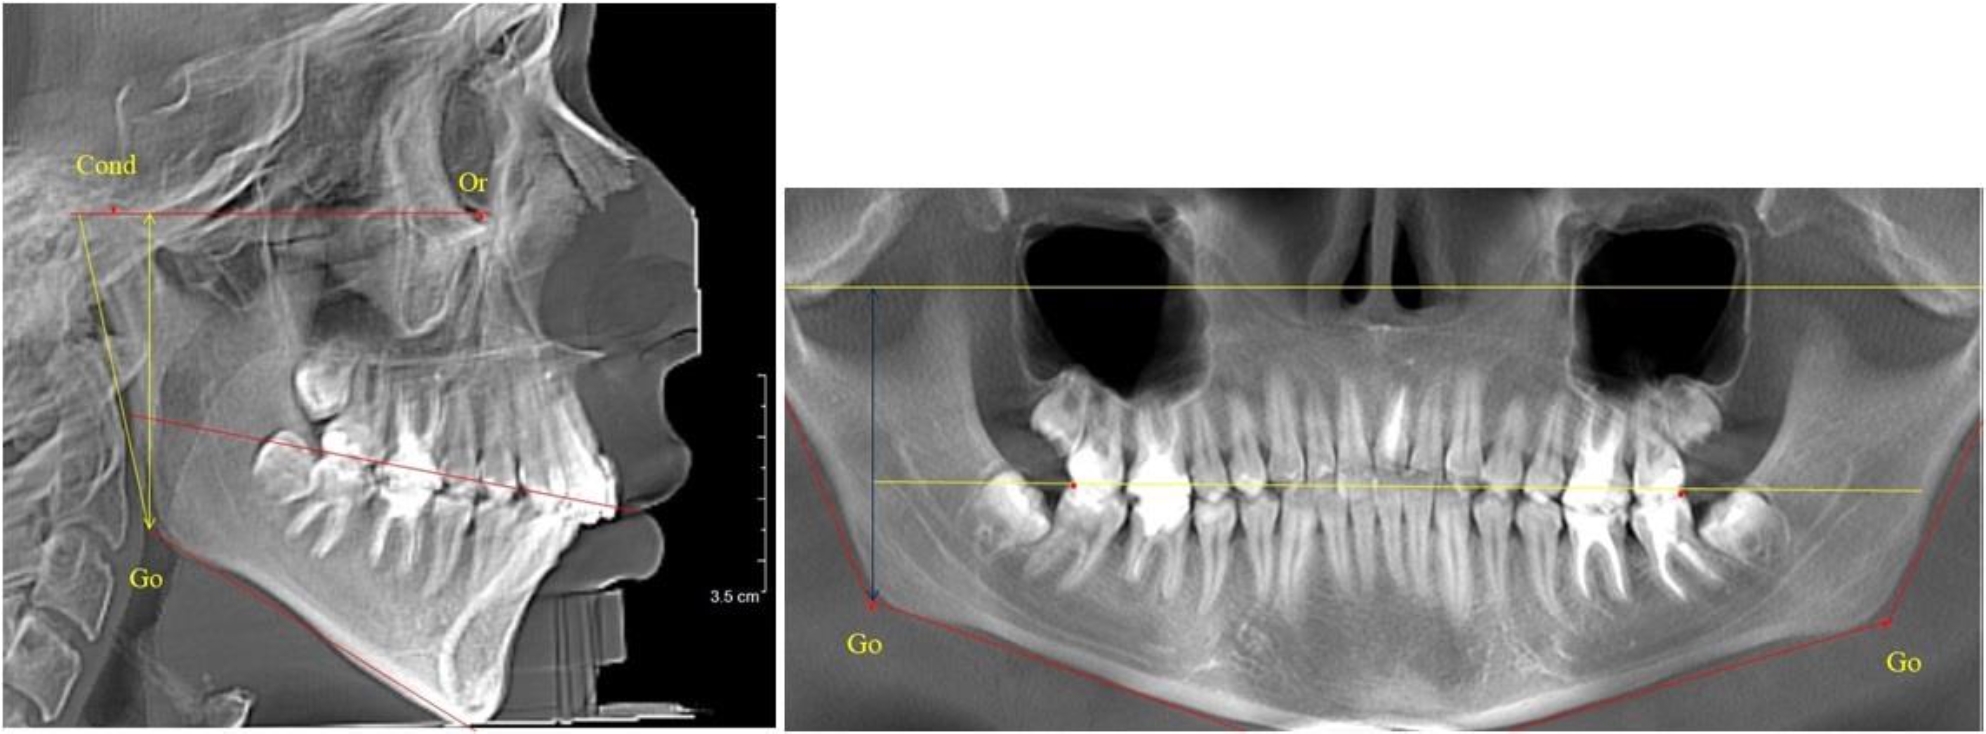

В 3-й группе были проанализированы 9 телерентгенограмм и 9 ортопантомограмм, что составило (8,49 ± 2,71) % от числа изученных рентгенограмм (рис. 3).

Рис. 3. ТРГ и ОПТГ пациента после смены молочных резцов

На всех рентгенограммах произошла смена молочных резцов постоянными. Окклюзионная линия делила ветвь на два отдела.

Высота ветви у детей у детей 3-й группы составляла (51,07 ± 2,72) мм, что было достоверно больше, чем у детей 1-й группы (р ˂ 0,05). При этом высота верхней окклюзионно-суставной части была (29,06 ± 1,44) мм, а нижней – (22,01 ± 1,59) мм. Высота верхней части была больше нижней, что и определяло особенности соразмерности частей ветви нижней челюсти в анализируемый возрастной период.

Относительные показатели соразмерности частей ветви нижней челюсти показали, что отношение высоты верхней части ветви к нижней в среднем составляло 1,32 ± 0,14. Отношение общей высоты ветви к верхней ее части составляло 1,75 ± 0,12, а отношение общей высоты ветви к нижней ее части было 2,32 ± 0,17, что и определяло особенности соразмерности частей ветви нижней челюсти в анализируемый возрастной период.

В 4-й группе были проанализированы 12 комплектов рентгенограмм, что составило (11,32 ± 3,08) % от общего числа. На всех рентгенограммах произошла полная смена всех молочных зубов постоянными. Окклюзионная линия делила ветвь на два отдела (рис. 4).

Рис. 4. ТРГ пациента после смены всех молочных резцов

Высота ветви у детей 4-й группы составляла (54,27 ± 2,59) мм, что было достоверно больше, чем у детей 1-й группы (р ˂ 0,05). При этом высота верхней окклюзионно-суставной части была (32,51 ± 1,72) мм, а нижней – (21,76 ± 1,42) мм. Высота верхней части была больше нижней, что и определяло особенности соразмерности частей ветви нижней челюсти в анализируемый возрастной период.

Относительные показатели соразмерности частей ветви нижней челюсти показали, что отношение высоты верхней части ветви к нижней в среднем составляло 1,49 ± 0,12. Отношение общей высоты ветви к верхней ее части составляло 1,67 ± 0,14, а отношение общей высоты ветви к нижней ее части было 2,49 ± 0,15, что и определяло особенности соразмерности частей ветви нижней челюсти в анализируемый возрастной период.